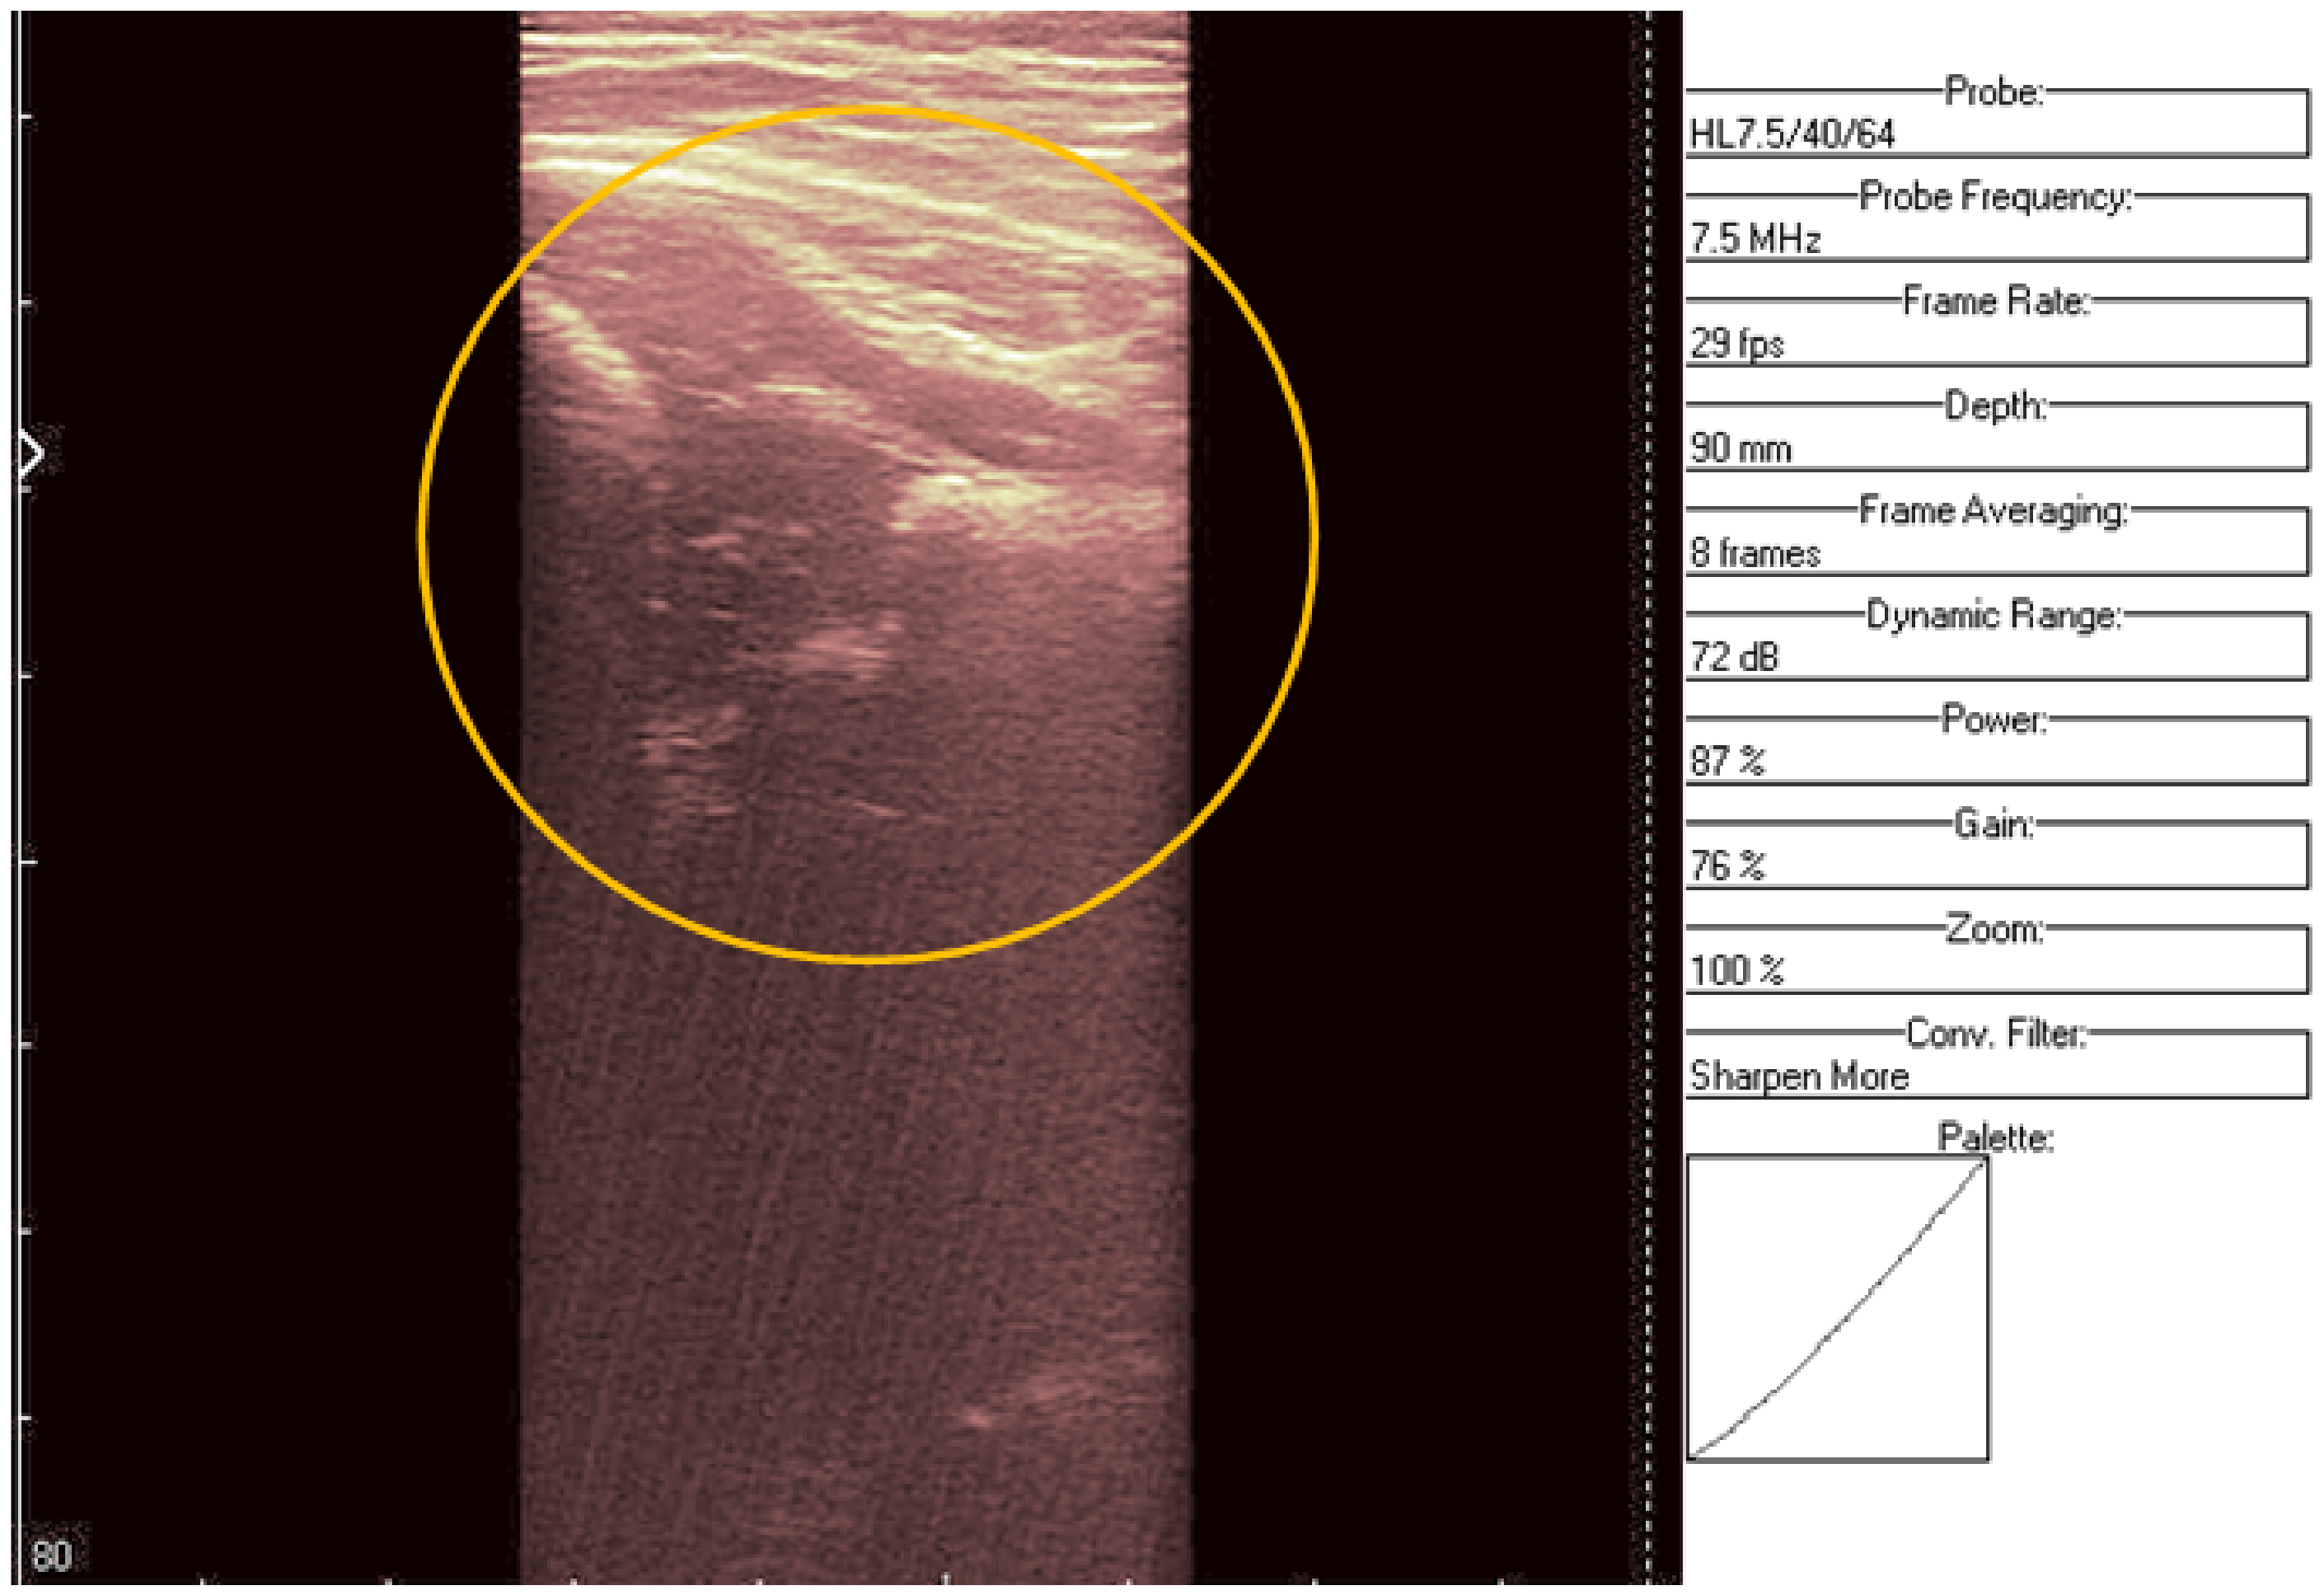

The second image (Figure 7 and Figure 8) is a hip socket sample taken from a female patient. Not many details can be noticed in the original image. The result of the proposed denoising system is presented in Figure 9. The anatomical structures can be observed more clearly and more detailed than before. In this study, we aimed not to debate the medical diagnoses, but to design an algorithm which can provide images at a better resolution, so as to help both the physician and the child patient.

Figure 7. Original data, Image 2.

Figure 8. Original data, Image 2, with added color palette and area of interest zoomed.